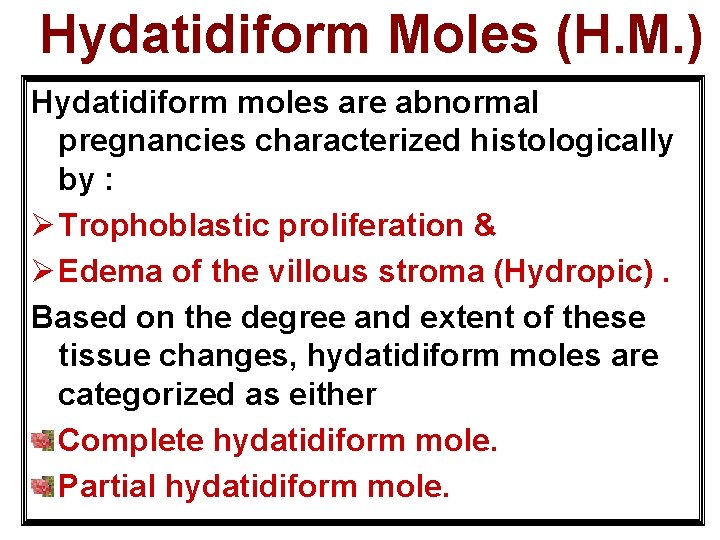

Hydatidiform Moles (H. M. ) Hydatidiform moles are abnormal pregnancies characterized histologically by : Ø Trophoblastic proliferation & Ø Edema of the villous stroma (Hydropic). Based on the degree and extent of these tissue changes, hydatidiform moles are categorized as either Complete hydatidiform mole. Partial hydatidiform mole.